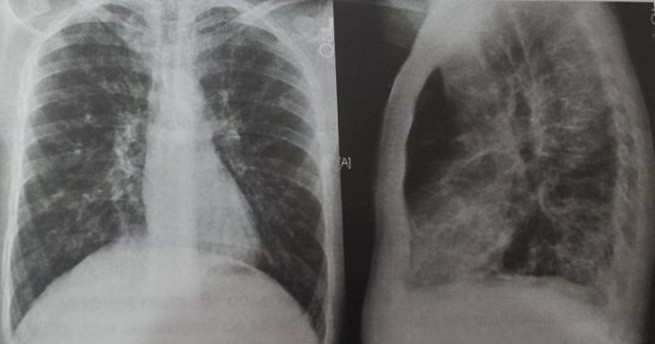

Fibroza Pulmonară și Colagenozele Pe Radiografia Toracică Proceduri Medicale